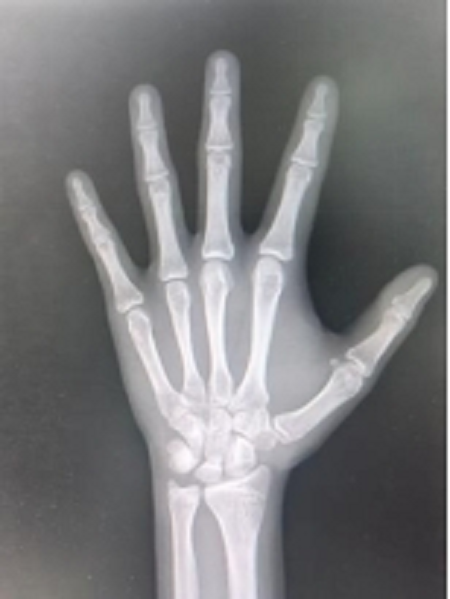

骨骺线尚未闭合状态